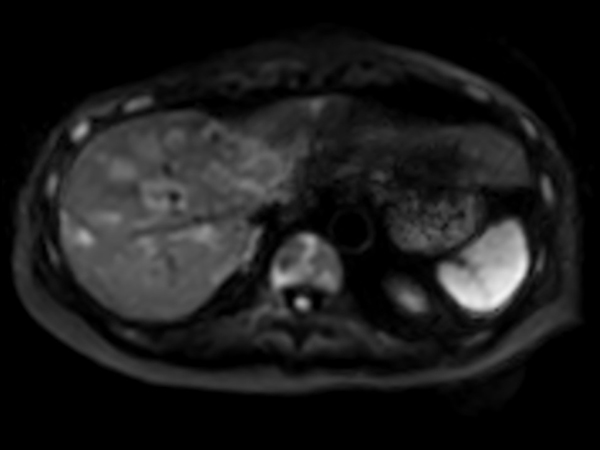

Axial Heavy T2w SSh FatSat